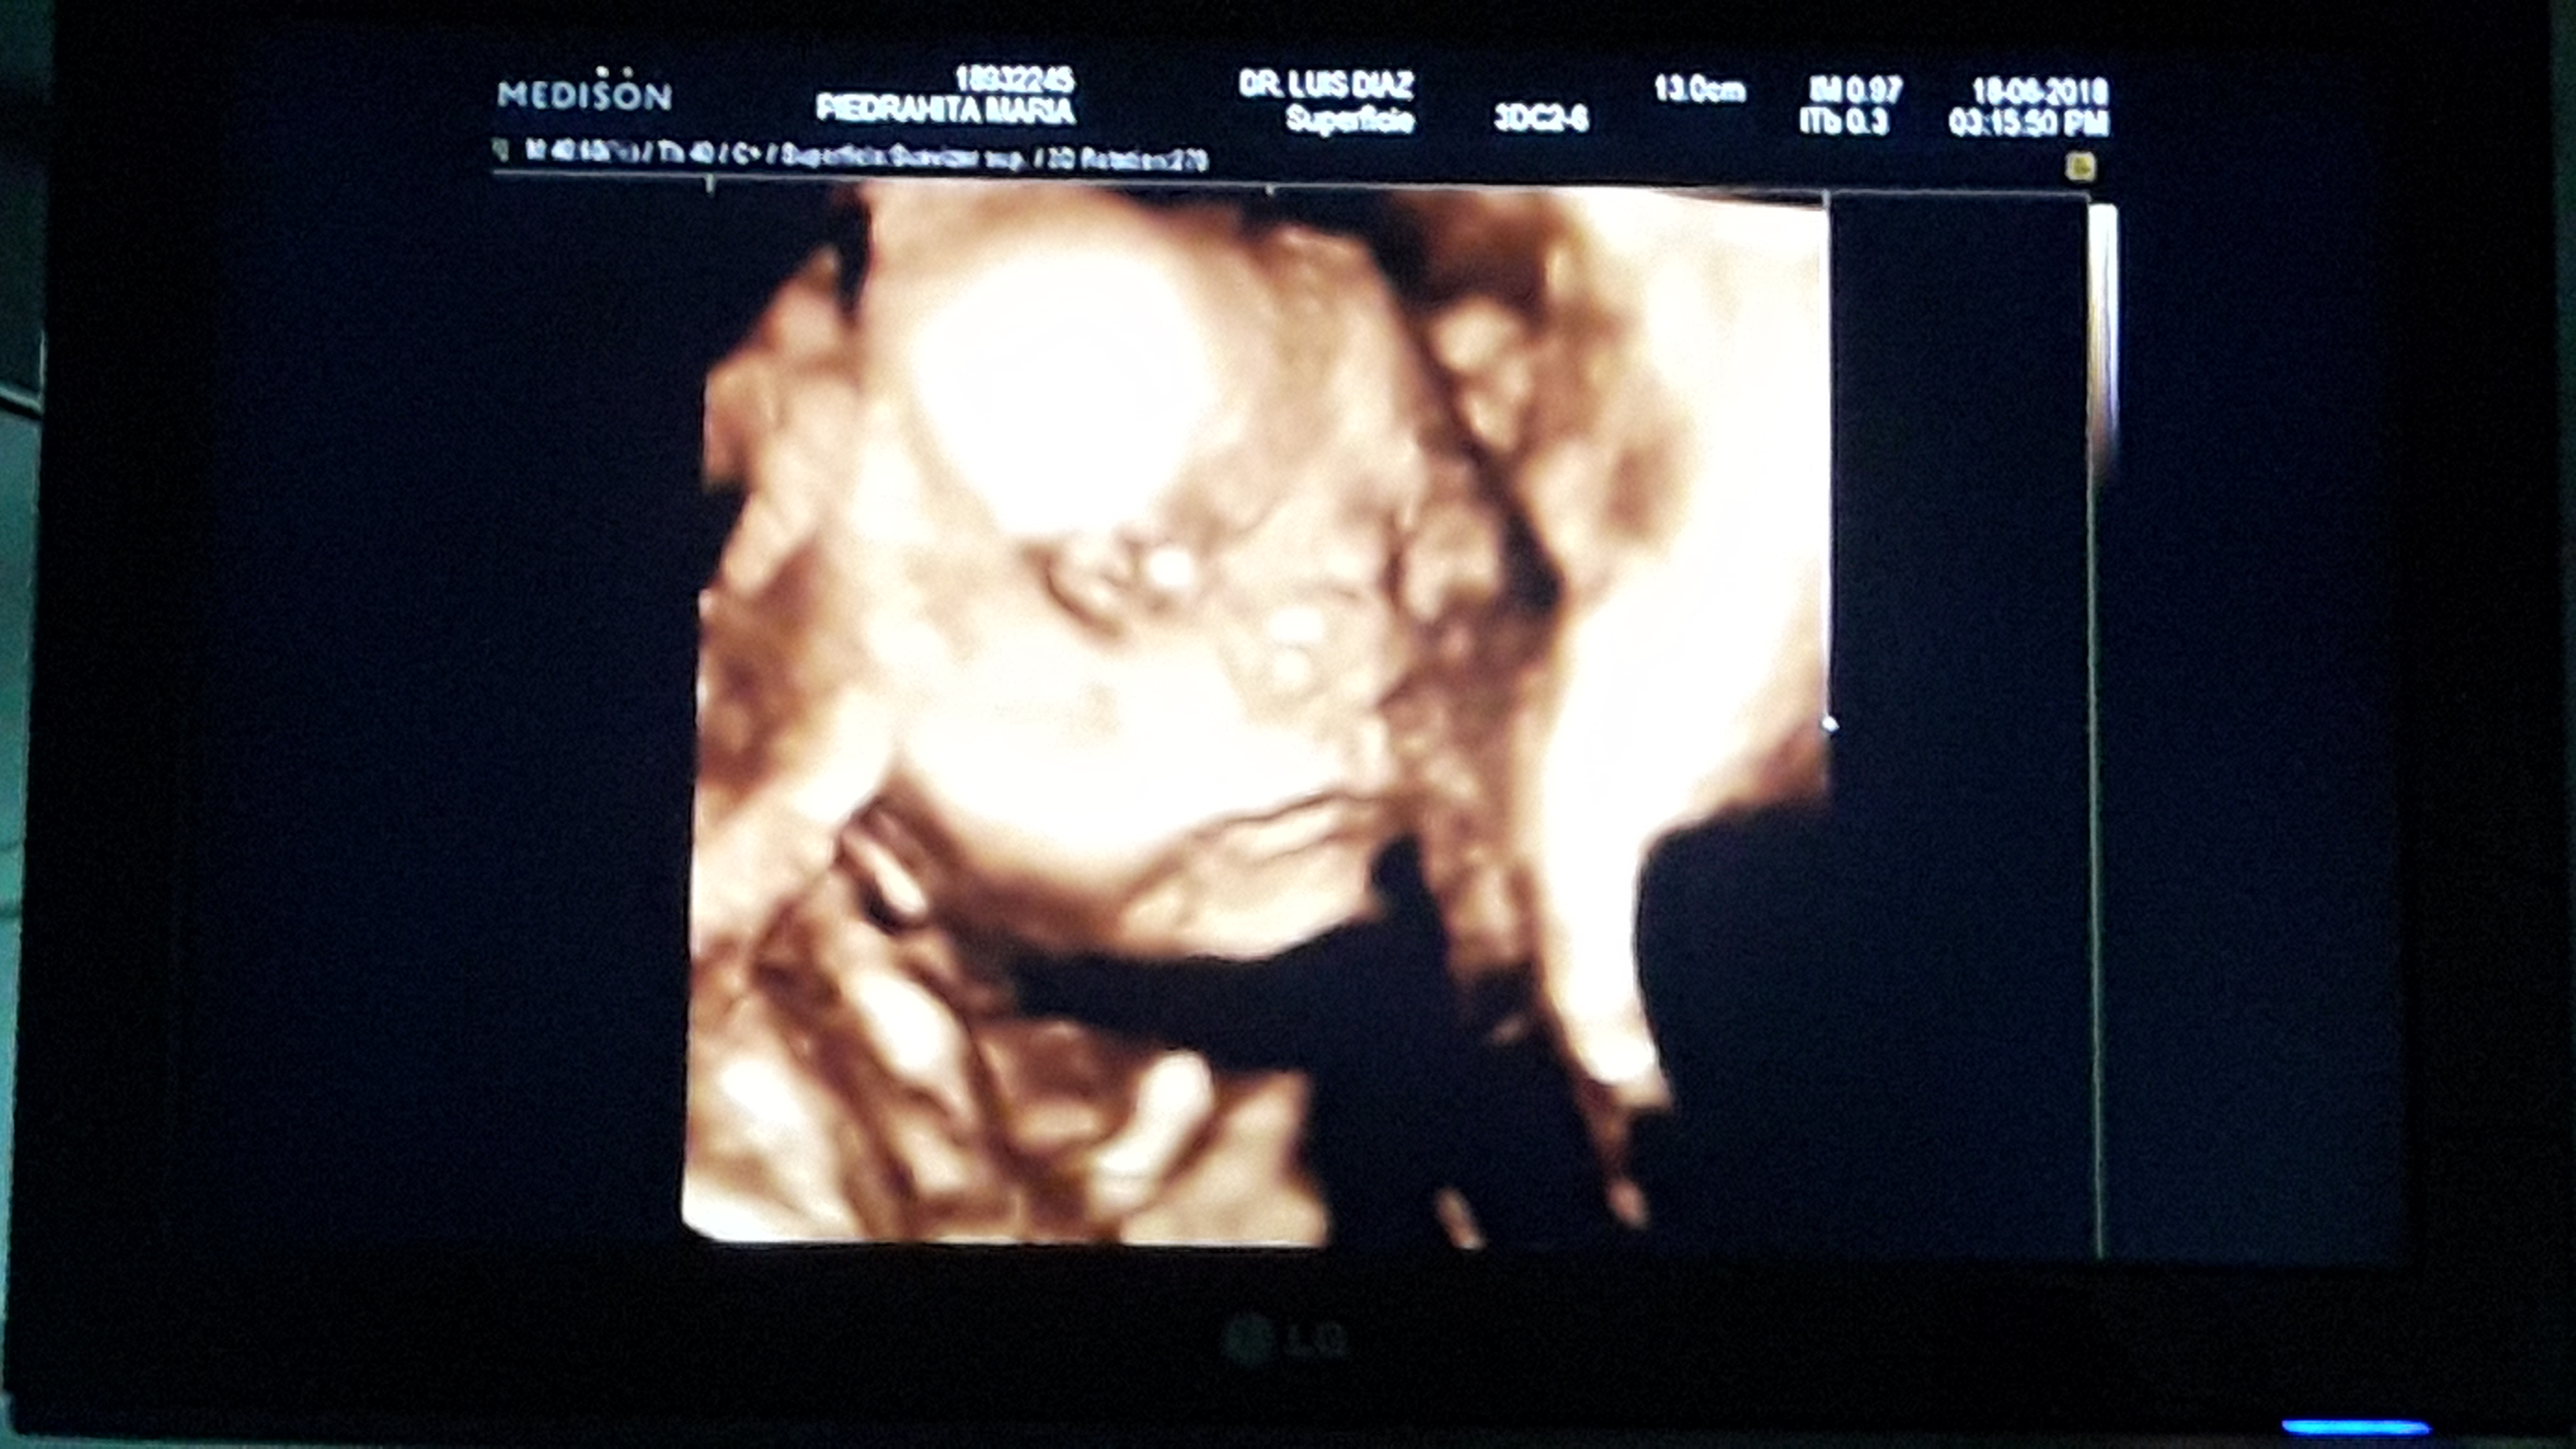

My mom just had an perinatal ecosonograms done on her to check me out and the doctor told her I'm weighting 1.2 pounds and measuring 12.99 inches he also said I have my stomach full cause I'm always eating is all I do all day lol. My mom also go to see my face for the first time ever and that was so exciting for her.

She says I look just like my dad, that I have his cheeks, his nose, his lips and that I just look like I'm a clone of his, I'm happy cause I want to be like him he is the best dad I could ever ask for so I'm excited to look just like him, I'm not sure is a good thing to have the same cheeks as my dad tho… cause my mom loves to bite his cheeks and now she tells me she will do it to me too.